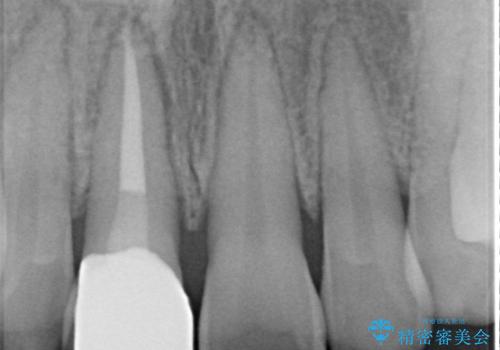

矯正の時使用していた仮歯を新調し、その後最終的な形を作ってから型取りを行います。

色もきれいだと患者様も満足されておりました。